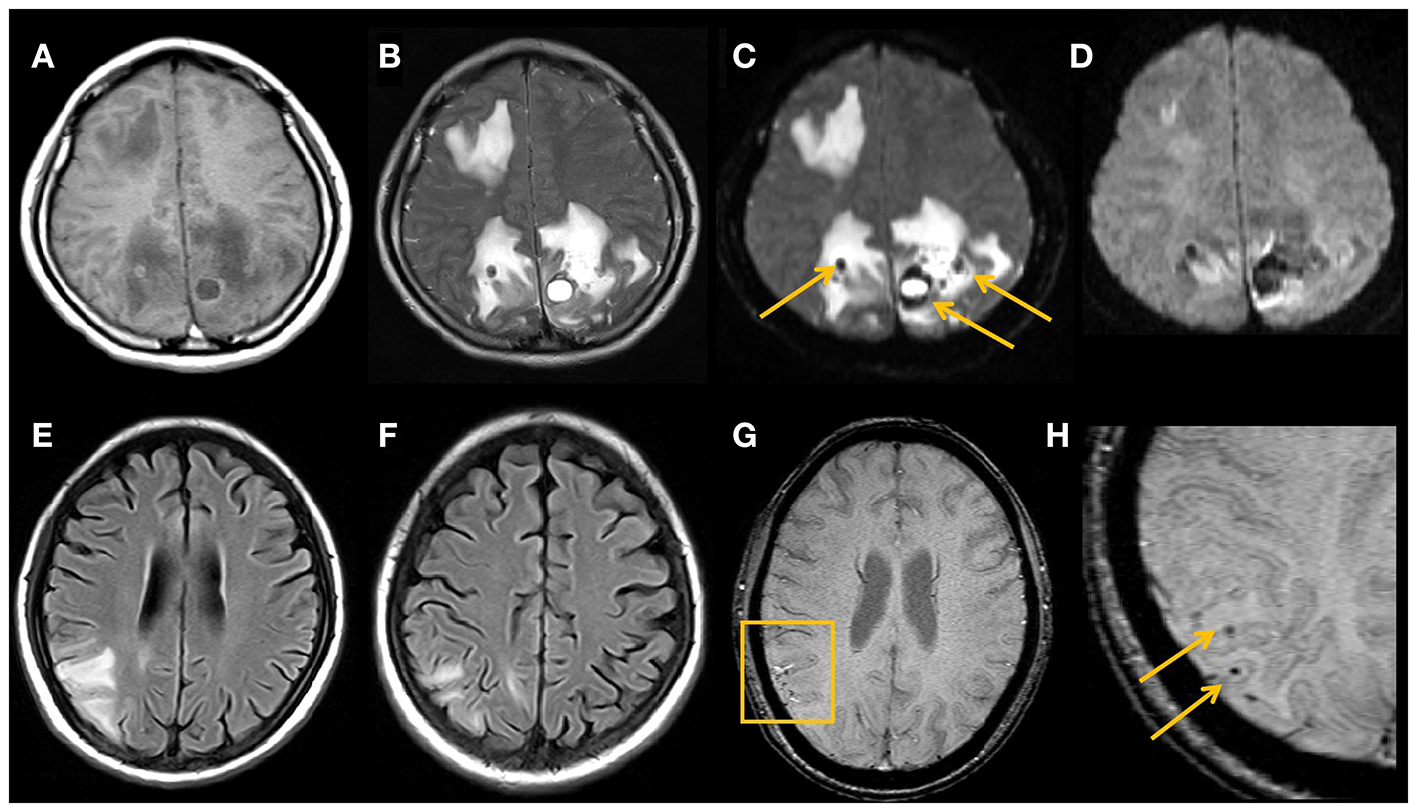

Figure 2

Typical MRI findings in hemorrhage secondary to PRES.Imaging studies in a 29-year-old female with lupus (A–D). MRI shows vasogenic edema in the right frontal lobe and bilateral parieto-occipital lobes, multiple hematomas are seen in the area affected by the edema, with heterogeneous high signal on T1WI (A), low signal on T2WI (B), low signal on DWI b = 0 images (arrows) (C), and magnetically sensitive artifacts of high signal around the hematoma visible on DWI b = 1,000 images (D). An 18-year-old young female with nephrotic syndrome (E–H). PRES-related right parieto-occipital cortical and subcortical edema on MRI FLAIR image (E,F), with multiple small microhemorrhages on SWI (arrows) (G,H).

Intracranial hemorrhage is a common complication of PRES, with an incidence of 15.2–64.5% (14, 15), and is associated with incomplete resolution of PRES (39). Intracranial hemorrhage manifests in three main patterns: intracranial hematoma, subarachnoid hemorrhage, and microhemorrhage, with intracranial hematoma being the most common (14). Susceptibility-weighted imaging (SWI) sequences are more sensitive than conventional T2 gradient-recalled echo imaging in detecting cerebral hemorrhage and microhemorrhage (Figures 2E–H), and 58% of patients with PRES combined with microhemorrhage were identified by SWI (15).

Vasogenic edema is a predominant feature of PRES, and the presence of restricted diffusion in some cases may represent the earliest irreversible sign: severe vasogenic edema progresses to cytotoxic edema, which further progresses to cerebral infarction (6). Covarrubias et al. (40) reported a group of 22 patients with PRES, 6 of whom developed diffusion abnormalities and 2 (9%) of whom showed progression to infarction at follow-up. Several studies have evaluated the clinical and radiological findings of patients with PRES and reported incomplete recovery and poor functional outcomes when PRES was associated with hemorrhage and infarction (3, 37, 41). Thus, early MRI features may be warning signs of a poor prognosis.